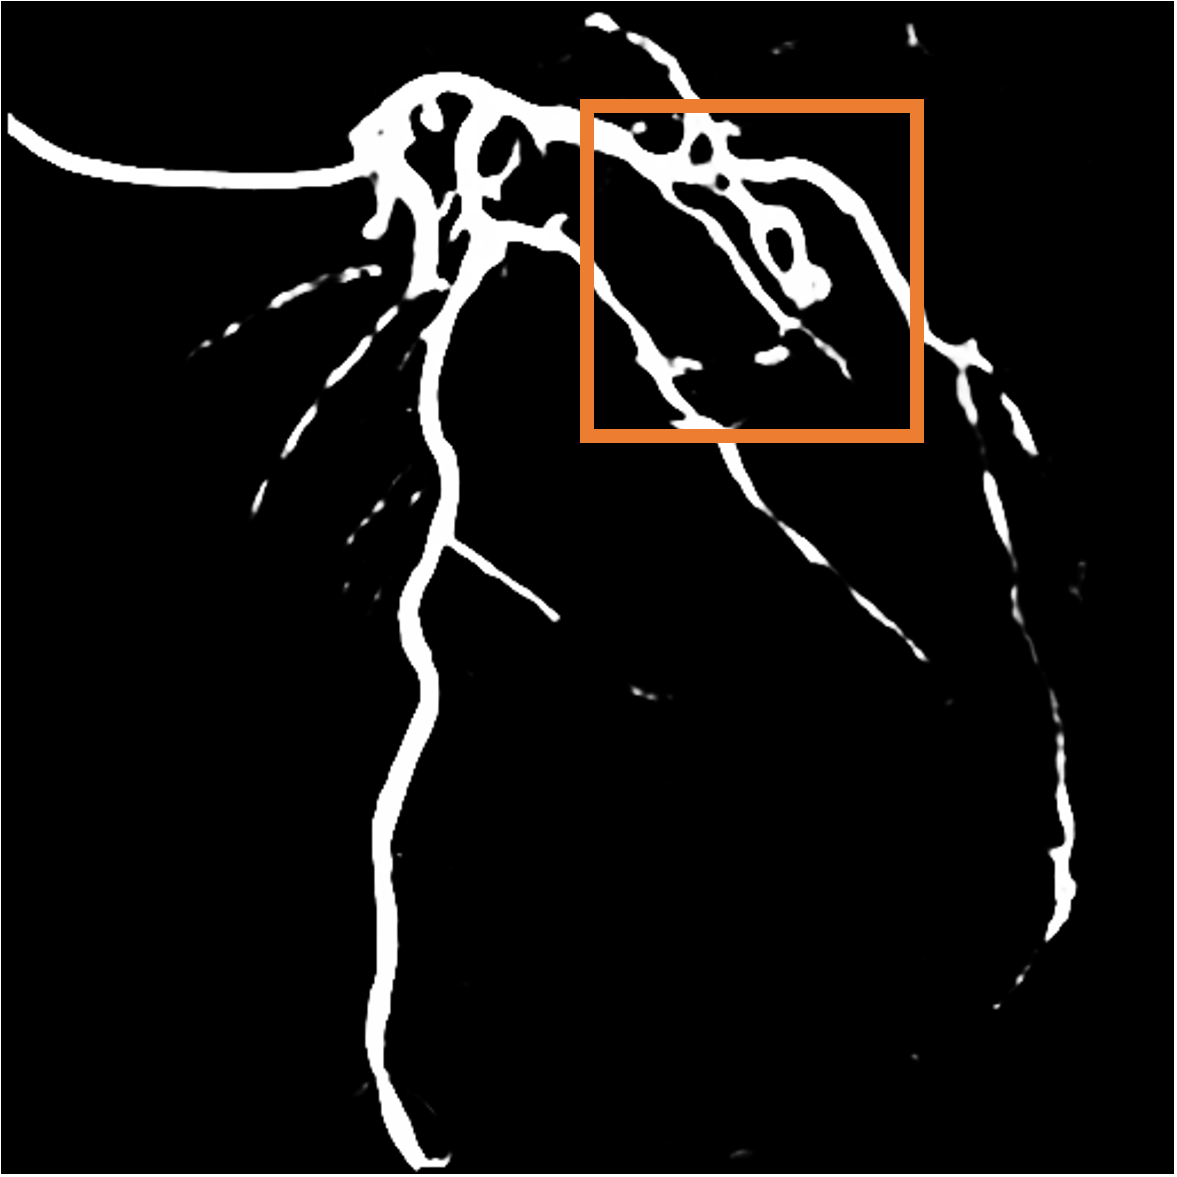

Layer separation bootstrapping.

To validate the effectiveness of the layer separation bootstrapping, we train foreground and background canonical images using the same representation. The results are shown in Table 2, where optimizing both foreground and background canonical images simultaneously leads to a decrease in the Dice score by 0.0877. The comparison is shown in Figure 9 (a), where the orange area indicates the difference between without and with Layer separation bootstrapping. The bottom-right corner shows a zoom-in patch, highlighting the significant effect of the bootstrapping step.